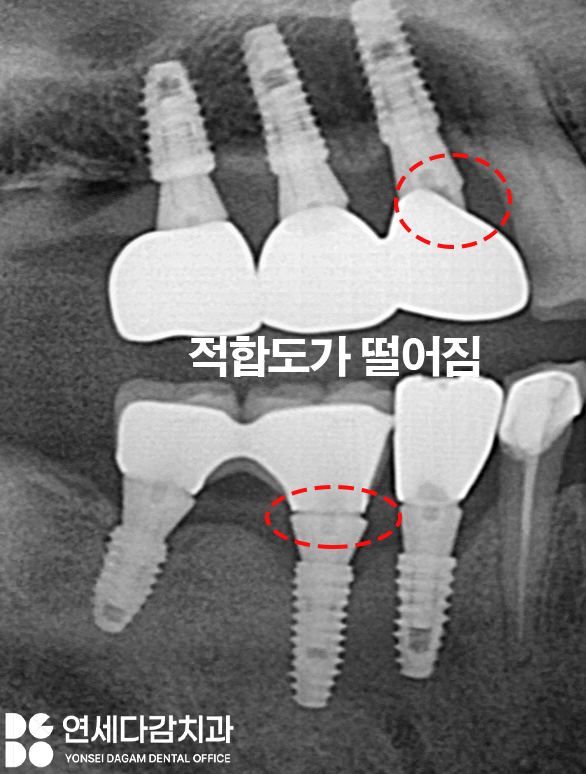

어버트먼트와 크라운 사이에 미세한 틈이 있으면

그 공간으로 세균이 들어오거나

음식물이 끼어들 수 있습니다.

기성 어버트먼트를 사용하면

본인의 잇몸에 맞춰 제작된 것이

아니기 때문에,

위와 같은 일이 생길 수 있습니다.

엑스레이 상에서 표시한 부위를

살펴보면 보철물이 살짝 뜬 것처럼

보이는 것을 볼 수 있죠.

이런 미세한 부적합은

육안으로 확인되지 않을 수 있어도

잇몸 밑으로 이런 형태를

가지고 있기 때문에

장기적으로 봤을 때

문제를 일으킬 가능성이 높습니다.

틈새에 세균이 번식하면

임플란트 주변에서 냄새가 나거나

잇몸에 염증이 생길 수 있습니다.

또한 음식물이 자주 끼면서

불편감을 호소하는 경우도 생깁니다.